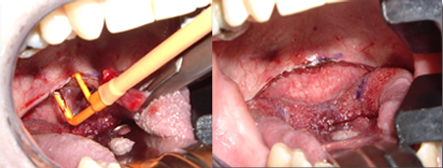

適用于細微、精細的切割如頭頸部,敏感部位皮膚的切割。

適合于皮下組織的切割和剝離。

特別是在運血較為豐富的部位。